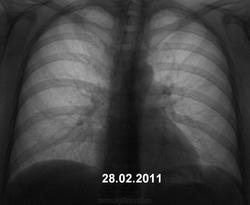

Женщина дисциплинированная, флюорографию не просрочила. Явных жалоб не предъявляет.

Хорошие иллюстрации. Понятно, что будет дообследование (учреждение не имеет особого значения) и верификация.

Мы, на довольно солидном материале убедились, что период даже в 6 месяцев не является гарантией стабильности. Были два случая, где промежуток был даже 4 месяца - "от нормы" до довольно значимой "специфики" (и не только "тубера").

Отдаю голосsmiley за саркоидоз.

да, похоже на саркоидоз

+1. Но, заключение должно быть верифицированно пункцией из доступного лимфатического узла.

Тоже - за медиастинальную форму саркоидоза.

изменений в лёгких   указывает на саркоидоз II стадии.

Я-то вообще сначало не понял ничего! Потом после коментариев почитал, тоже стал склоняться к саркоидозу, но меня смущает отсутствие клинических проявлений, а тень, что рассположена справа у корня мне напоминает увеличенный сосуд.

подобную картину могут давать хронический лимфолейкоз, метастазы различных злокачественных опухолей и др. Здесь необходима  быстрая морфологическая верификация. Игорь Иванович поступил правильно, так как при неблагоприятной эпидемической и социально-экономической ситуации  на постсоветском пространстве туберкулеза много. Я недавно такой случай показывал в игре "Поставь диагноз №5".

1. Это ключевая фраза. 2. Саркоидоз, зачастую не имеет клинических проявлений, поэтому выявляется при профилактических исследованиях. 3. Поглядите внимательно и постарайтесь запомнить, коллега, так выглядят корни при саркоидозе. Практически типичная картина, почти без диф. диагноза.